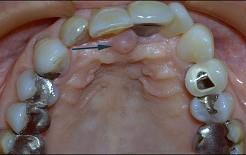

无牙颌患者的口内特征为 ( )

无牙颌患者的口内特征为 ( )![]()

A牙列缺失

B牙冠缺损

C牙体缺失

D牙列缺损

E牙体缺损